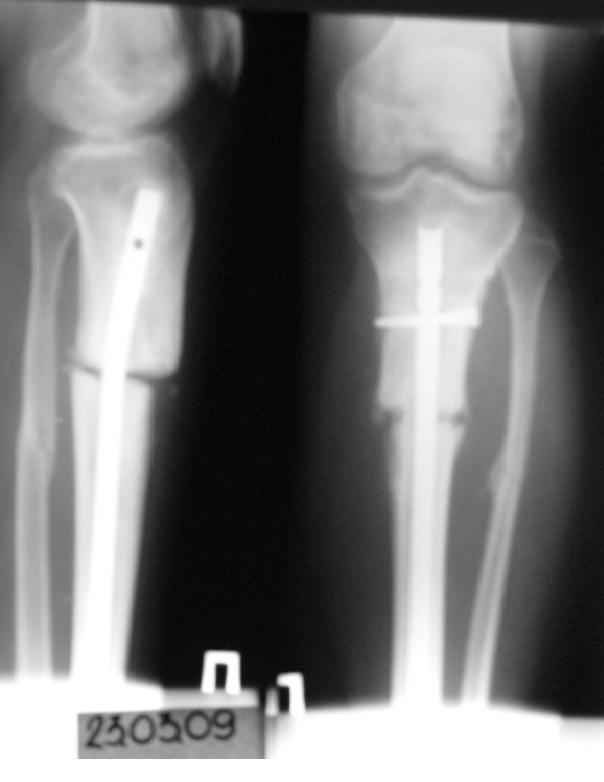

История следующая: женщина (медработник)сбита машиной 7.06.08 - о.перелом обоих костей голени в/3 со смещением. В ПДО ПХО раны,вытяжение за пяточную кость. После заживления раны 20.06.08 выполнен остеосинтез блокирующем стержнем. в течение первого месяца после травмы сохранялась субфебрильная температура на фоне приема антибиотиков. Затем температура стабилизировалась.Б-ая как положено ходила в гипсе на костылях. На контрольных рентгенограммах консолидация не достигалась, иммобилизация продлевалась. Пациентка на себе опробовала все препараты костной регенерации. В марте удален один из фиксирующих винтов. На сегодняшний день идет 11 мес. после травмы. Решается вопрос о инвалидности. Буду благодарен за предложения по дальнейшему ведению больной. Операция?

Сегодня мы имеем консолидированный перелом малоберцовой кости, являющийся распоркой и отстутствие консолидации большеберцовой кости, и ваша динамизация гвоздя, выполненная с опозданием не ришила проблем.

Основной причиной несращения считаю неправильный выбор метода остеосинтеза(очень высоко).Идеальным выбором для такого перелома считаю LSP пластина или стержневой апарат.Что делать?

Не показан нижний конец гвоздя. Винты надо было убирать из него, зачем из верхнего-то отломка.

Сейчас надо перештифтовать. При удалении взять посев. Не просто рассверлить старый канал и поменять гвоздь на больший, а устранить все смещения при помощи отклоняющих винтов. Рассверлить надо. Малоберцовую, наверно, лучше пересечь внизу.

На рентгенограмме несоответствия кортикальной аппозиции в виде потерянного сегмента и пластическая деформация малоберцовой, это знак оставленного ротационного смещения во время операции.

Движение вокруг проксимального гвоздя означает разгибательно-сгибательную нестабильность в проксимальной части большеберцой.